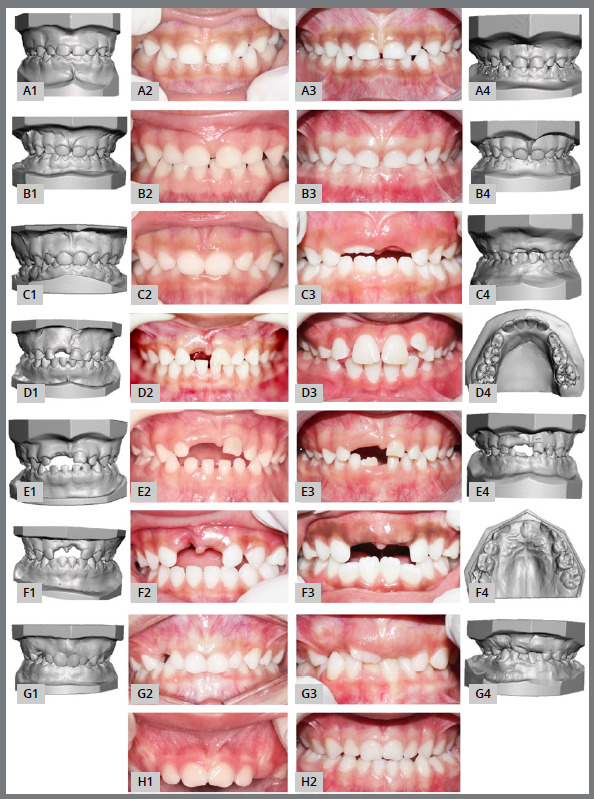

Results: Individuals' mean age at baseline was 2.93 (± 1.18) years. No statistically significant differences were observed in the missing tooth space in the group with tooth loss during the 24 months of follow-up (p > 0.05). Arch perimeter, arch length, arch width, intercanine length and intercanine width did not show differences between the groups (p > 0.05). Qualitative photographic evaluation revealed other changes in the dental arches and occlusion, such as exfoliation and eruption of deciduous teeth, eruption of permanent teeth, self-correction or establishment of malocclusion, among others.

Conclusion: The results suggest that the premature loss of deciduous anterior teeth does not affect the perimeter, length and width of the dental arches; however, other alterations that lead to malocclusion could be established.